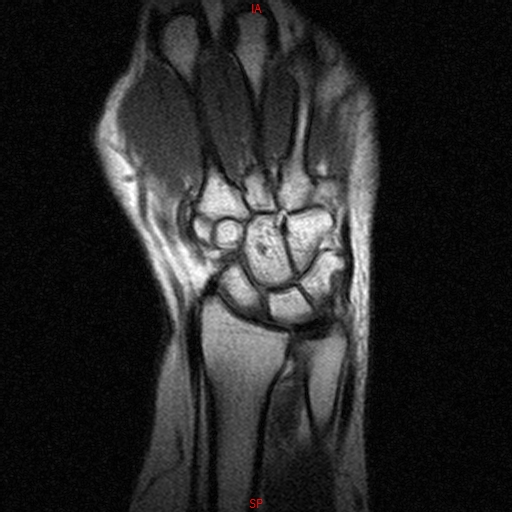

• RESONANCIA PATOLÓGICA DE MUÑECA - FRACTURA ESCAFOIDES